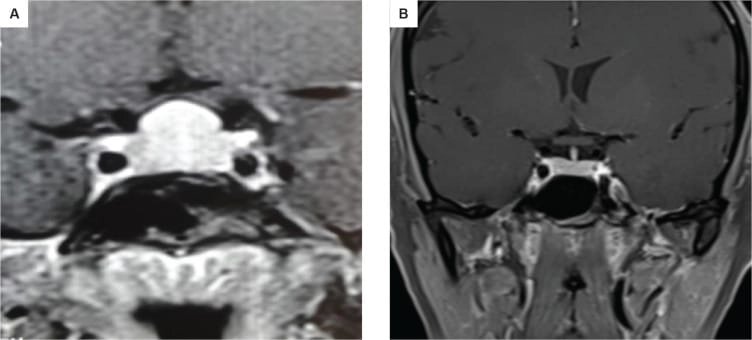

তবে পিটুইটারি হাইপারপ্লাসিয়া দেখা যায় প্রাইমারি গনাডাল, অ্যাডরিনাল বা হাইপোথাইরয়েডিজমের মত এন্ড অর্গান ইনসাফিসিয়েন্সিতে। বিশেষ করে, অব্যবহৃত প্রাইমারি হাইপোথাইরয়েডিজমে পিটুইটারি হাইপারপ্লাসিয়া পূর্বের ধারণার তুলনায় অনেক বেশি দেখা যায়। ২০১৯ সাল পর্যন্ত এরকম ১০৫টি কেস রিপোর্ট করা হয়েছে। এই ধরনের হাইপারপ্লাসিয়া গম্বুজ-আকৃতির (dome-shaped) হয়ে অপটিক কায়াজমাকে চেপে ধরতে পারে, যার ফলে অপারেশনের প্রয়োজন পড়তে পারে—যেমনটা আমাদের তৃতীয় কেসে ঘটেছিল।

কেস ১: একজন ১৬ বছর বয়সী কিশোরী প্রাথমিক অ্যামেনোরিয়া ও খর্বাকৃতিজনিত কারণে এমআরআই করার পর একটি পিটুইটারি টিউমার শনাক্ত হয় এবং তাকে অস্ত্রোপচারের জন্য রেফার করা হয়। তবে তার রক্ত পরীক্ষায় পাওয়া যায় TSH ছিল 119.20 এবং Free T4 ছিল 4.14 pmol। এই অস্বাভাবিক মাত্রার কারণে এটিকে একটি থাইরোট্রোফ হাইপারপ্লাসিয়া হিসেবে বিবেচনা করা হয় এবং তার চিকিৎসা শুরু হয় এবং ৬ মাসের মধ্যে উচ্চতা ১২৪ থাকে বেড়ে ১৩১ সেমি হয় এবং তার ঋতু ও শুরু হয় এবং MRI-তে টিউমার সম্পূর্ণভাবে অদৃশ্য হয়ে যায়।

কেস ২: একই রকমভাবে, ১৫ বছর বয়সী আরও একজন কিশোরী অল্প উচ্চতা ও টিউমার সন্দেহে নিউরোসার্জেনের কাছে রেফার করা হয়। তার TSH ছিল 100 এবং MRI-তে একটি ডোম-আকৃতির টিউমার দেখা যায়। যাকে ওষুধের চিকিৎসায় সত্য জীবনে ফিরিয়ে আনা হয় এবং ৬ মাসে তার উচ্চতা বৃদ্ধি পায় ও নিয়মিত মাসিক শুরু হয়। MRI-তে টিউমার সম্পূর্ণ অদৃশ্য হয়ে যায়।

চিকিৎসক তথা আবিষ্কারক সত্যম তিনটি কেসের বিষয় নিয়ে যখন তুলনা করতে নিলেন এবং পুরনো সৃষ্টি ঘাটতে শুরু করলেন তখন তিনি দেখতে পান সবগুলি ক্ষেত্রেই একই রকম সাদৃশ্য অর্থাৎ পিটুইটারি গ্রন্থি মাঝের অংশ এই গ্রন্থি দেখতে খানিকটা প্রজাপতির মতোই এবং তার মাঝের অংশের (প্রজাপতির দেহের উপরের অংশ মাথার মতই দেখতে) উপরের ভাগ সব ক্ষেত্রেই ডোমের মত বা গম্বুজ আকৃতির। তিনি এই ডোম বা গম্বুজ আকৃতি হওয়ার কারণ বিশ্লেষণ করতে গিয়ে দেখেন পিটুইটারির সামনের অংশ যেখানে থাইরোট্রপগুলো থাকে, যেখান থেকে এই টিউমারটি হয়। আর যখনই এটি বাড়বে তখন টমের মতনই তৈরি হবে। অর্থাৎ গম্বুজ আকৃতির। আর সেখান থেকেই ডোম-সাইনের উৎস অর্থাৎ আবিষ্কার।

MRI-তে এই হাইপারপ্লাসিয়া সাধারণত গম্বুজ-আকৃতির ও সমমিত হয় এবং হোমোজেনাস সিগনাল ইন্টেনসিটি দেখায়, যেখানে সাধারণ নন-ফাংশনাল পিটুইটারি অ্যাডেনোমা নানা আকার ও অসমতা নিয়ে দেখা যায়।